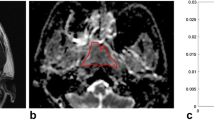

An ROI was manually drawn by a radiologist (specialized in head and neck radiology) to contour the border of NPC on each slice in order to obtain the total tumour volume. The total tumour volume was then calculated on the basis of the segmentation method. Each ROI was contoured on STIR T2W images (Fig. 1a) and co-registered to DW images (Fig. 1b) for analysis using Image J (NIH, Bethesda, MD). Each lesion was measured twice in two separate sessions at 2 weeks apart to ensure reproducibility. The obtained parameters for each lesion were then calculated on a pixel-by-pixel basis and expressed as means of the whole volume analysed.

The intraobserver agreement was good with a kappa value (κ) for α and DDC of 0.81 and 0.77 respectively. The mean tumour volume was 1,334.29 ± 1,978.01 mm3 (53.2–10,098.60). The mean values of α and DDC in the low and high stage groups for AJCC staging are summarized in Table 2 and represented in respective box plots (Fig. 2a and b). Their respective optimal cut-off values upon ROC curve analyses are summarized in Table 3 and shown in Fig. 3.